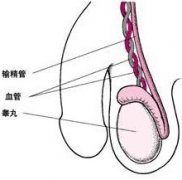

都市男性睾丸生精功能障碍出现的病因

生精功能障碍有哪些危害?

生精功能异常会出现什么症状?

生精功能障碍要做哪些检查?